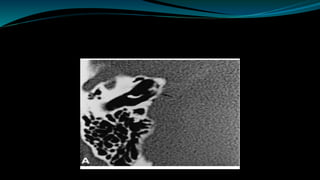

Radiological assessment  Detectanomalies of bony labyrinth  Narrow IAM  Enlarge vestibule aqueduct  Facial nerve dehiscence  Low laying dura  High jugular bulb • Detect labyrinthine ossification • Early fibrotic obstructions. • Identification of cochlear agenesis • Cochlear nerve agenesis • Potency of cochlear duct • Acoustic tumor • CNS abnormalities HRCT MRI